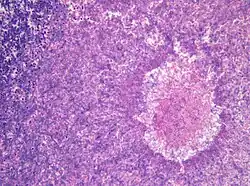

Aspergillomas complicating tuberculosis: multiple aspergillomas within large cavitary lesions of tuberculous origin. | |

Although most fungi—and especially Aspergillus—fail to grow in healthy human tissue, significant growth may occur in people whose adaptive immune system is compromised, such as those with chronic granulomatous disease, who are undergoing chemotherapy, or who have recently undergone a bone marrow transplantation. Within the lungs of such individuals, the fungal hyphae spread out as a spherical growth. With the restoration of normal defense mechanisms, neutrophils and lymphocytes are attracted to the edge of the spherical fungal growth where they lyse, releasing tissue-digesting enzymes as a normal function. A sphere of the infected lung is thus cleaved from the adjacent lung. This sphere flops around in the resulting cavity and is recognized on x-ray as a fungus ball. This process is beneficial as a potentially serious invasive fungal infection is converted into surface colonization. Although the fungus is inactivated in the process, surgeons may choose to operate to reduce the possibility of bleeding. Microscopic examination of surgically removed recently formed fungus balls clearly shows a sphere of dead lung containing fungal hyphae. Microscopic examination of older lesions reveals mummified tissue which may reveal faint residual lung or hyphal structures.[5]